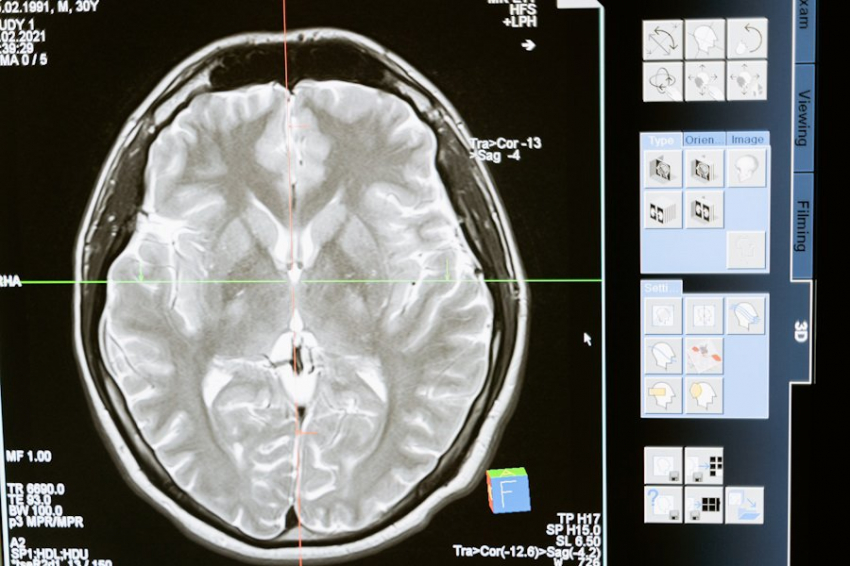

Система представляет собой комплексное решение, состоящее из двух ключевых компонентов. Первый компонент - это копирующее устройство, которое фиксирует и анализирует движения здоровой конечности пациента или воспроизводит действия врача-реабилитолога. Второй компонент - роботизированный экзопротез руки, способный точно повторять движения, задаваемые копирующим устройством. Такой подход направлен на восстановление поврежденных нейронных связей в коре головного мозга пациента.

Статистика показывает, что нарушения двигательной активности наблюдаются у 80% пациентов, перенесших инсульт, причем половина из них не способна самостоятельно передвигаться или нуждается в постоянной помощи. Эти данные подчеркивают острую необходимость в эффективных реабилитационных технологиях.